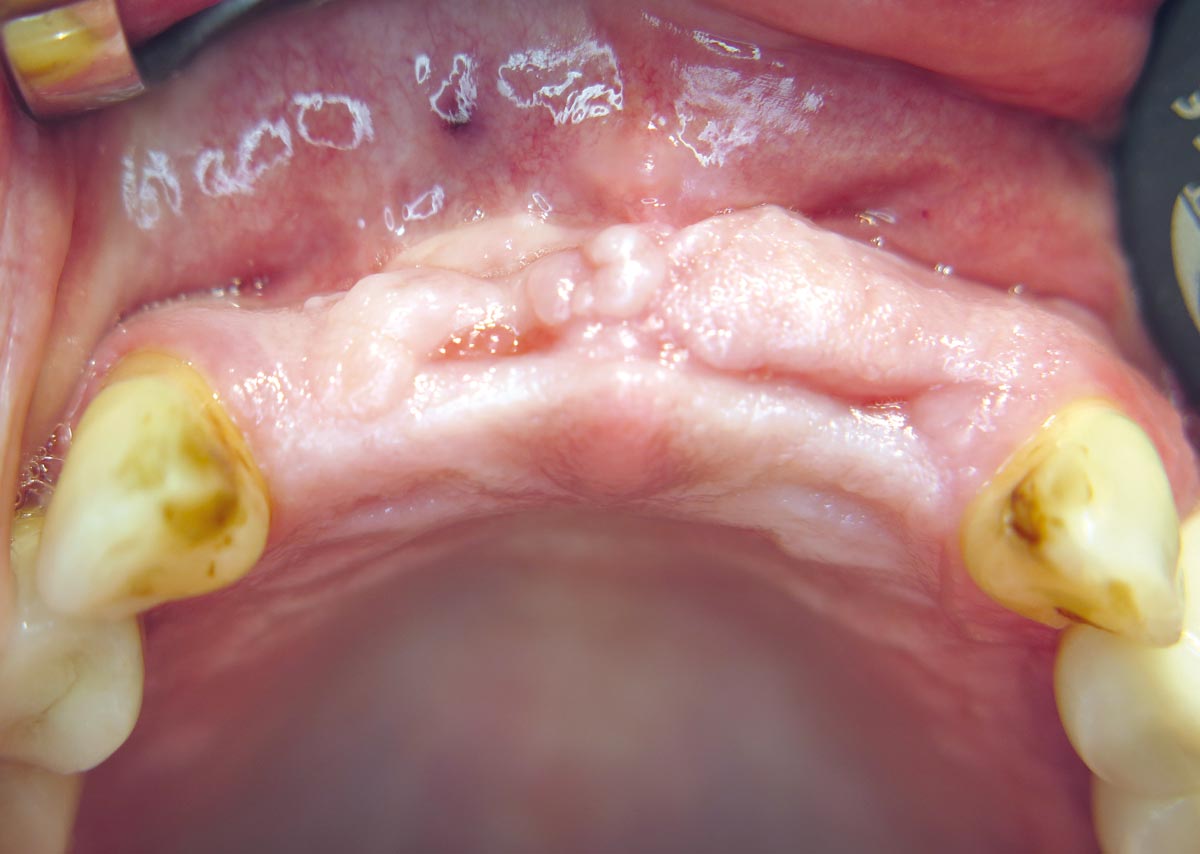

01 / 22 - Initial clinical situation – missing bonein regio 11, 12, 21, 22 and scarred soft tissue